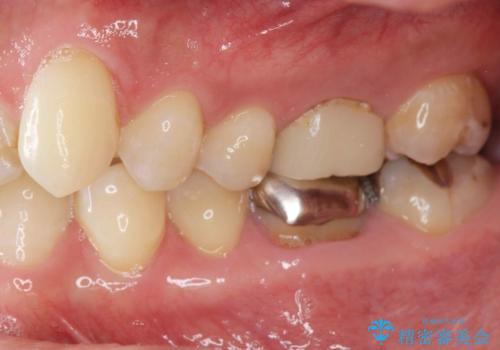

- 食事のたびに食べ物が詰まる銀歯のやりかえを希望され来院されました。

歯ぐきと銀歯の間に大きな凹みがあり、食べ物が詰まりやすく、また虫歯にもなりやすい状況です。